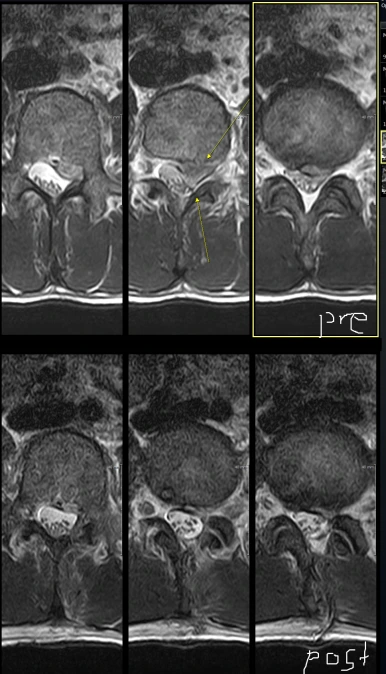

위에 사진 5장은 수술 전, 아래 5장은 수술 후입니다.

내시경으로 보면서 수술 깔끔하게 진행되었고, 디스크는 거의 다 제거되었습니다.

디스크가 up migrated 되어있어서 뼈를 많이 갈아낼 수도 있다고 생각되었는데 (hemilaminectomy 가능성) 지난번처럼 30도 내시경 덕분에 손상부위 거의 없이 안전하게 수술 진행됐습니다.

MRI 좌측 axial 영상 보시면 facet이 거의 온전히 보전된걸 볼 수 있습니다.